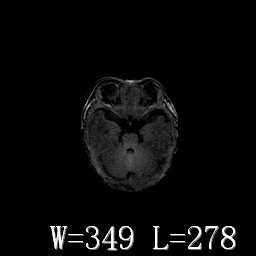

新生儿正常颅脑

hie?

脑干形态欠规则,信号增高,不知怎么解释?

脑干背侧面t1高信号是,新生儿正常已经髓鞘化好的部位